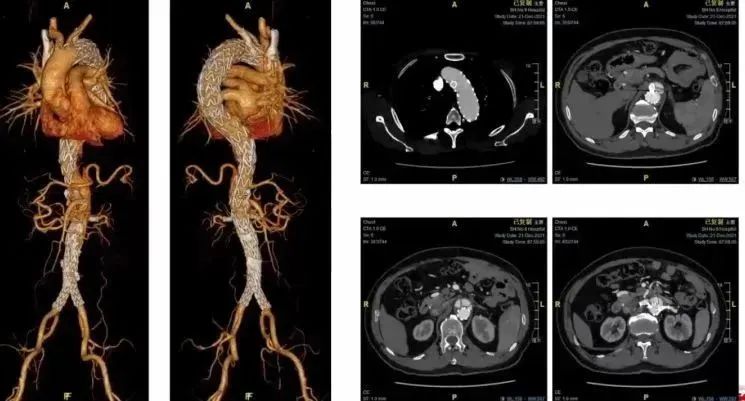

患者女,82岁,主动脉夹层,突发胸背痛1天。该患者行保留左锁骨下动脉的杂交手术。若以后需要做内脏动脉重建,需要建立重要通路,I期在近端锚定区做杂交手术也相对安全。

回顾性分析了43例进行激光原位开窗-TEVAR手术治疗A型夹层的患者及多个病例的技术细节。对于远端锚定区,也尽量一期做覆膜支架的延伸,限制性覆膜支架对于患者的真腔灌注,重塑和血栓化也会有较好的结果,降低截瘫的风险,同时降低远期内脏再干预率。